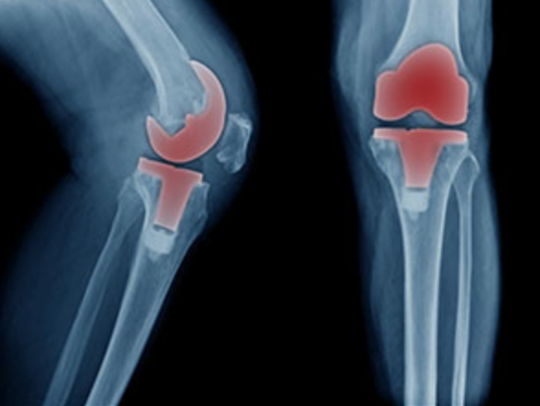

Reeducationが行う変形性膝関節症へのアプローチ

繰り返される膝関節痛の最終形態がOPE

膝が内側に入る結果、痛みが出て変形する

先ほども記載しましたが、ヒトのカラダは1回 悪くなったものを変える方法は手術しかありません。

しかし、いかに「手術しない! 手術させない!」ためには、「膝の機能を修正すること!」「歩行時に膝が内側に入らないように動作を修正!」するしか方法はありません。

上記の写真をみてわかるように膝が内側に入っているのがわかります。

膝が内側に入る事で内側の靭帯が伸ばされたり、膝の中のある半月板への圧縮ストレスが高まったりとすることによってドンドンドンドン膝の構造が悪化していきます。